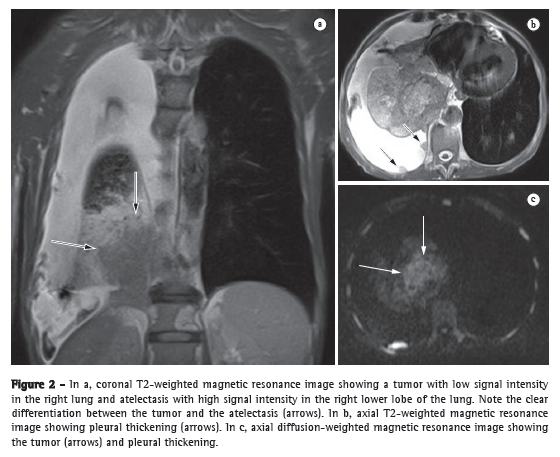

In the tumor-node-metastasis (TNM) staging system, the T stage (depth of tumor invasion) is the primary determinant of the gravity of neoplasia.(12) For the depiction of the pericardium, heart, and mediastinal vessels, MRI is superior to CT and can therefore be indicated in specific situations, such as superior vena cava obstruction, invasion of the myocardium, or the spread of the tumor into the left atrium via the pulmonary veins.(13) In addition, MRI can allow lung cancer to be distinguished from secondary changes due to atelectasis or pneumonitis.(12) In T2-weighted MRI sequences, post-obstructive atelectasis and pneumonitis often show higher signal intensity than does the central tumor (Figure 2).(12)